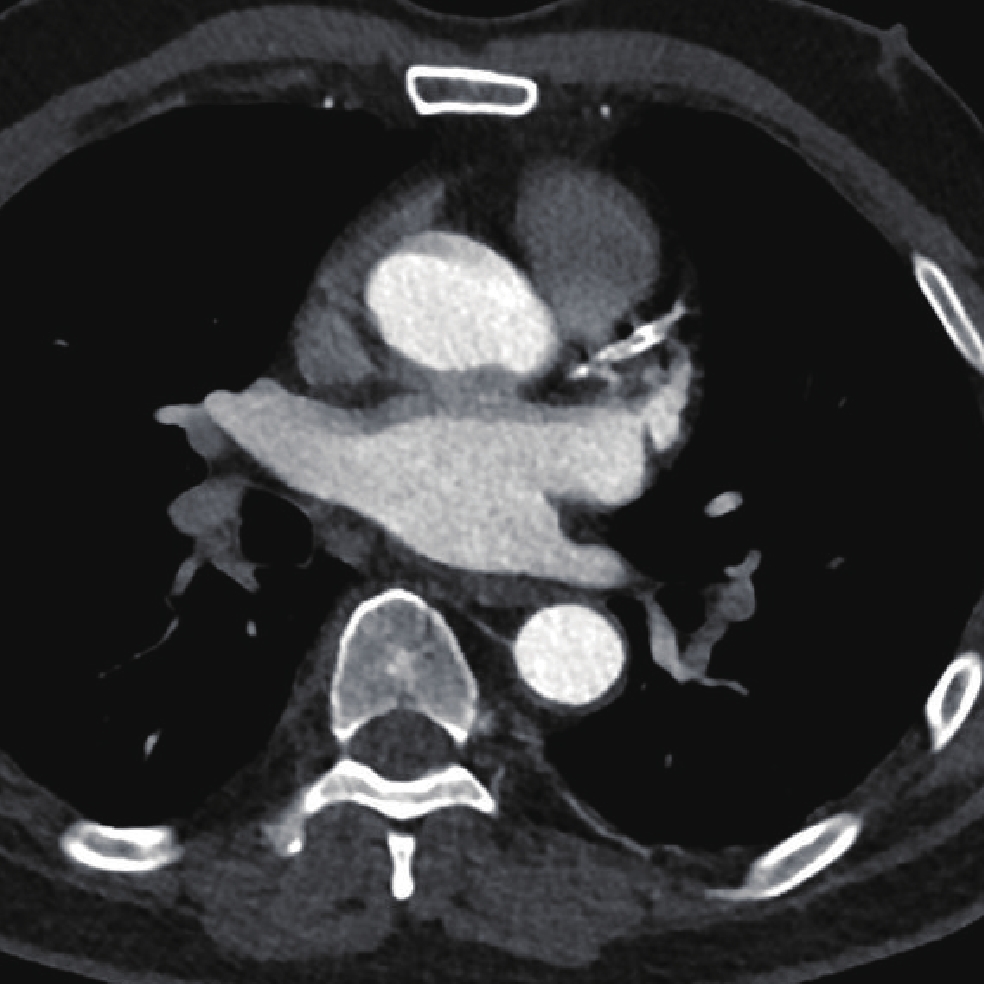

• 摘要: 目的:探讨不同扫描模式对胸主动脉CTA图像质量和辐射剂量的影响。方法:回顾性分析未应用心电门控技术的30例胸主动脉CTA(组1,对照组),使用回顾性心电门控的30例冠脉CTA重建舒张期(组2)和收缩期(组3)时相,30例应用宽曝光脉冲前瞻性心电门控技术(组4)共4组图像的质量和辐射剂量。分别记录、计算4组的图像质量客观指标CT值、噪声、CNR和辐射剂量指标CTDIvol。对图像质量进行四分法主观评价。对主客观指标分别统计分析。结果:客观指标CNR组1与组2、3、4均有差异,组2、3、4间均无差异;主观评分两两比较组2~4显著高于组1,组2~4间无差异。非门控组(组1)、回顾门控组(组2和组3)和前瞻门控组(组4)的CTDIvol分别为13.70(11.87,16.58)、12.62(10.03,15.01)、11.54(8.92,15.56),差异无统计学意义。结论:在胸主动脉CTA中推荐使用窄曝光脉冲的前瞻性心电门控收缩期或舒张期扫描,可显著提高胸主动脉心脏段图像质量并降低辐射剂量。

Abstract: Objective: This study aimed to compare the effects of different scanning modes on image quality and radiation dose in thoracic aortic computed tomography angiography (CTA). Methods: The image quality and radiation dose of 30 cases of thoracic aortic CTA (Group 1, control group), 30 cases of retrospective CTA diastolic phase (Group 2) and systolic phase (Group 3), and 30 cases of wide-exposure pulse prospective electrocardiogram (ECG) (Group 4) were retrospectively analyzed. The CT value, noise, contrast-to-noise ratio (CNR), signal-to-noise ratio (SNR), and radiation dose (volume CT dose index CTDIvol) were recorded and measured. The image quality was evaluated subjectively using the four points method. The subjective and objective indicators were analyzed statistically. Results: No differences were observed in the objective indexes of noise, CNR and SNR among the groups. The subjective score of pairwise comparison of Groups 2~4 was significantly higher than that of Group 1, and no difference was observed among Groups 2~4. The CTDIvol values of the non-gated group (Group 1), retrospective gated groups (Groups 2 and 3), and prospective gated group (Group 4) were 13.70 (11.87,16.58), 12.62 (10.03,15.01), and 11.54 (8.92,15.56), respectively, without a statistically significant difference.